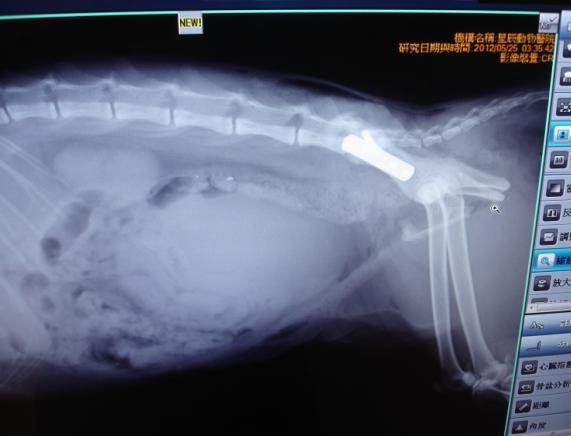

主題: 三重車禍骨盆骨折移位癱瘓復健貓-第2次申請醫療費用 申請者姓名: 敏大哥 花色: 申請日期: 2012-08-15 16:02:48 申請者部落格: 申請者臉書網址: 所在縣市/合作醫院: 台北市/星辰動物醫院 治療費用: 36010元 需求人數: 39人 已結案 (2013-06-27 13:29:16) 報名人員: 陳明蘭(已付款)、Latte(已付款)、Joy(已付款)、大雨(已付款)、大雨(已付款)、zatti(已付款)、Huan Feng Tz(已付款)、Ginny Cat(已付款)、Choco Chen(已付款)、Choco Chen(已付款)、E(已付款)、永顗(已付款)、KO.PON(已付款)、Orak Yeh(已付款)、Vicky Wu(已付款)、Lydia(已付款)、F.y. Yang(已付款)、M.K(已付款)、謝佩芳(已付款)、CANDY(已付款)、陳玉君(已付款)、陳玉君(已付款)、Jessica I-Chin Pan(已付款)、Angie Chao(已付款)、Nikki、Nikki、戴小戴(已付款)、戴小戴(已付款)、Maru Pang(已付款)、Joanna Tang(已付款)、陳曉玫(已付款)、Shirley Chen(已付款)、Water(已付款)、五雞(已付款)、楊小馥(已付款)、蔡摳摳(已付款)、Mandy Wang(已付款)、Reinette(已付款)、Reinette(已付款)、大喵、Meow Purr Purr、Emily Chou x2(已付款)、 候補人員: Tracey Kao、邱冬梅、Faith Lin、Hoya、小舟、 動物病情說明: 三重網友李先生通報發現路倒貓, 求援"請支持流浪貓TNR計劃協會", 由我救援送醫至星辰動物醫院. 吳醫師研判疑似車禍造成癱瘓,拍X光確診這隻母貓已懷有身孕了! 腹腔胎兒約2週. 右側骨盆骨折. 左側腸薦關節移位. 需要開刀打骨板和骨釘接合.

5/22入院後先點滴輸液調養身體. 於5/25進行3個手術-(1)左側腸薦關節移位,手術復位植入骨螺絲釘. (2)右側骨盆骨折,手術植入骨板並縫合完成. (3)骨折將子宮體切斷,胚胎受損, 導致體內大出血. 手術取出子宮卵巢胚胎. 因為重症外科手術費用較高, 所以於6/1先針對外科手術醫療費35,000元募款. 醫助編號:374. 醫助內容請參考網址: